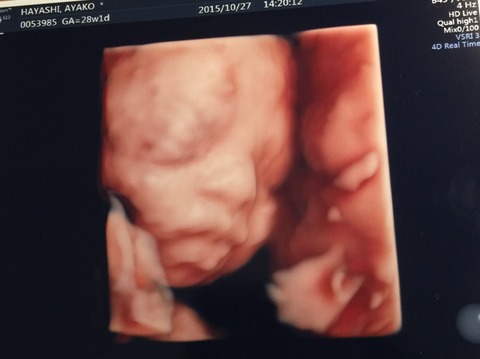

…って事で、昨日は撮影後に4Dエコーなるものを見る為に妻と病院へ。

タイミング次第では、全く顔が見えない事もあるそうで我が子の顔が見れるのか?少しドキドキしてたんですが…

無事?ご対面出来ました(^ ^)

結構動いてたので手足が邪魔して見えなくなったりしましたが…

手も足も元気な証拠かな?とか思いつつ、右手の指がなんとなく5本確認できたのでハサミは握れるな!とかも密かに思ったりしてました( ^ω^ )

最後には、ニッコリ笑ってくれた…様な気がしましたが…えぇ、既に親バカですσ(^_^;)

初め見た時は、ヴォルデモート感がスゲェな…とか思いましたが、後半は不思議と可愛く思えてきましたもんね( ^ω^ )

少しずつではありますが、我が娘がそこに居てその娘の親になるんだなぁ…と実感する機会が増えてきました。